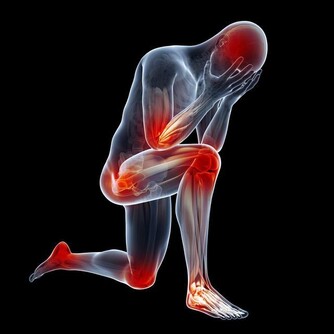

1、長期處在壓力中,健康最容易亮起紅燈。(健康隱患:慢性疲勞綜合徵)

2、對流行性感冒病毒防衛能力最差。(健康隱患:流行性感冒)